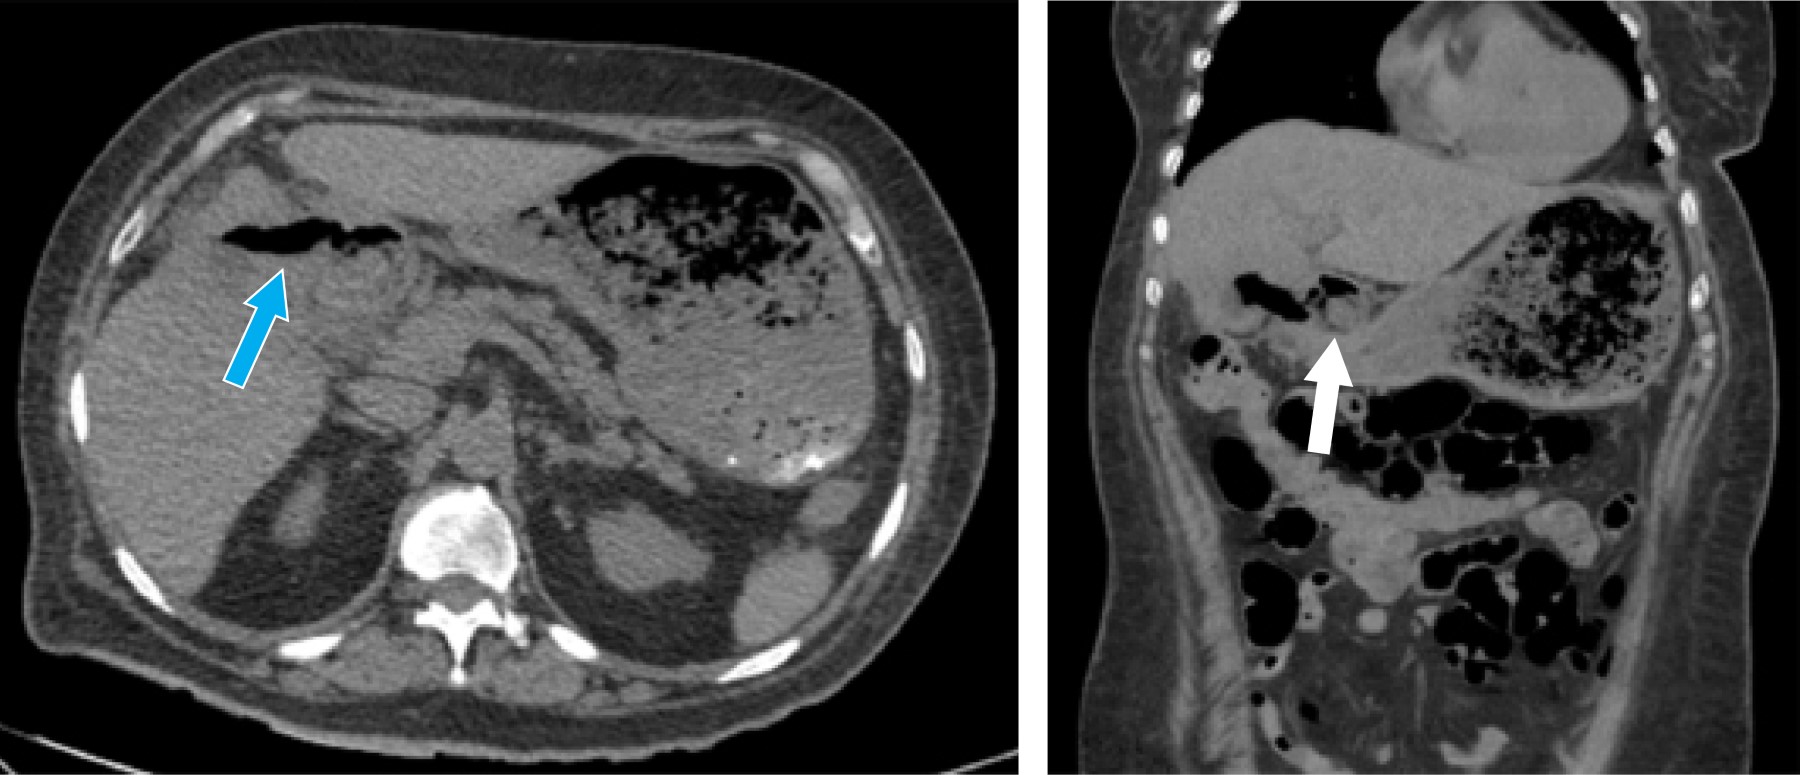

After surgery, parenteral nutrition was started. On the fifth postoperative day, a computed axial tomography (CT) scan with oral contrast showed no evidence of contrast medium leakage (Figure 4), and it was decided to restart the oral route.

Figure 4